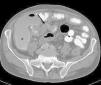

Chemotherapy-induced enteritis: Institutional experience and review of the literature

Enteritis inducida por quimioterapia: experiencia institucional y revisión bibliográfica